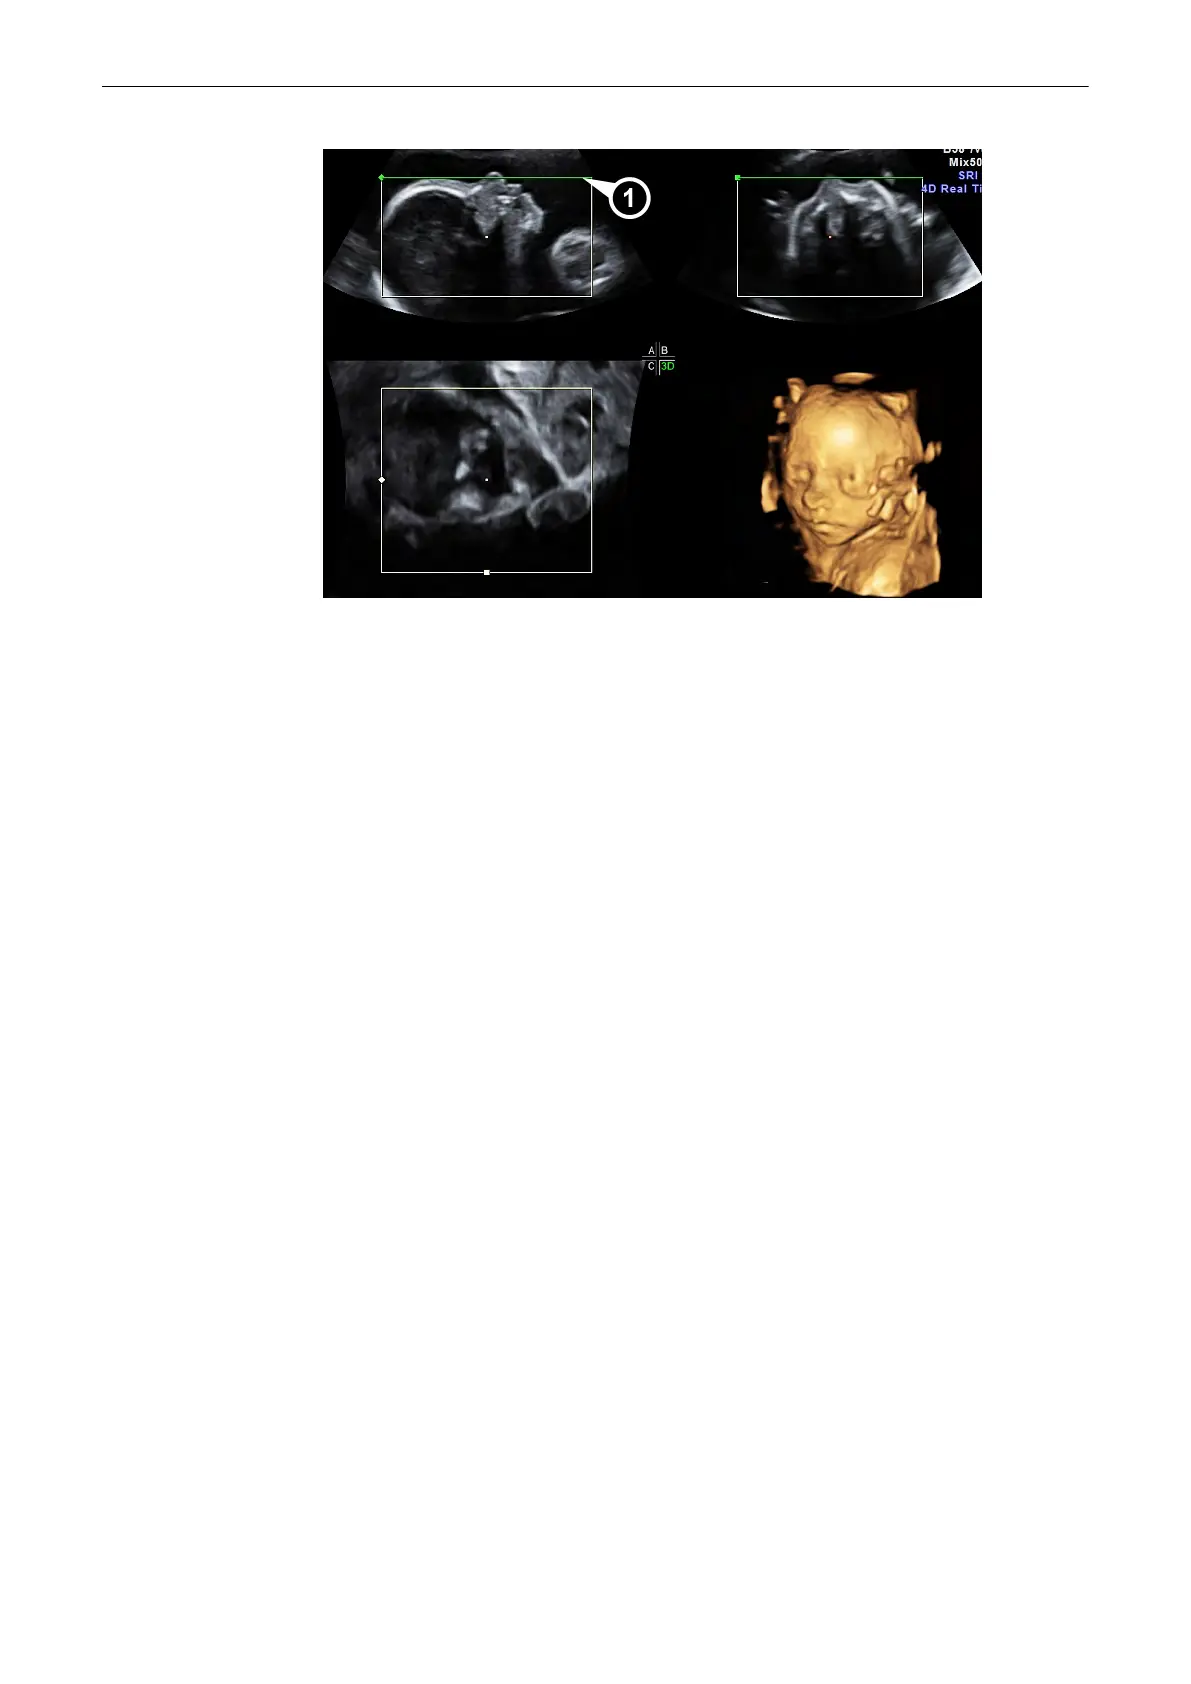

9.7 Volume Cine

The 4D VolCine function allows the user to save and work with the acquired Volumes.

Depending on the memory and volume size up to 128 volumes can be displayed. The

advantage of working with 4D VolCine is that during the acquisition the user can concentrate

on the acquisition itself. After acquisition the user has the possibility to review and work on the

acquired volumes.

After [Freeze] the system switches automatically to freeze mode and the “Volume Cine” menu

appears. The selected format and the last acquired Volume will be present on the monitor.